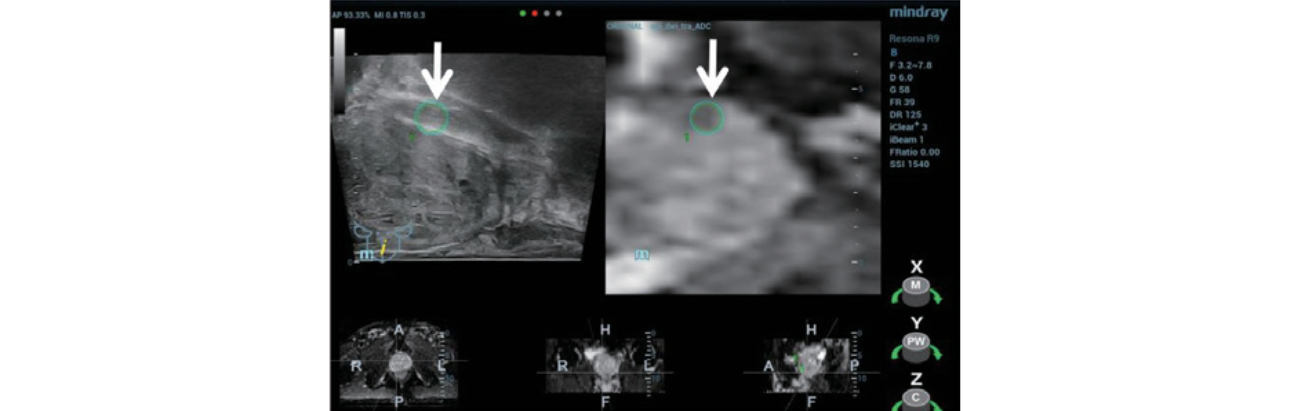

Step 2:??????? iFusion ?????? ???? TRUS/MRI ???? ?? ? ??(Figure 3) ?? ?? ???(Figure 4).

Step 3:???? ??? ???? ?? ???? ??? ?? MRI ??(Figure 5)? ???? ??? ?? ???(CEUS)? ??????.

Step 4:?TRUS/MRI ?? ??? 12 points systemic needle ????? ??? ? ???? ??? 3??? ??? ??? ?? ????? ???????.